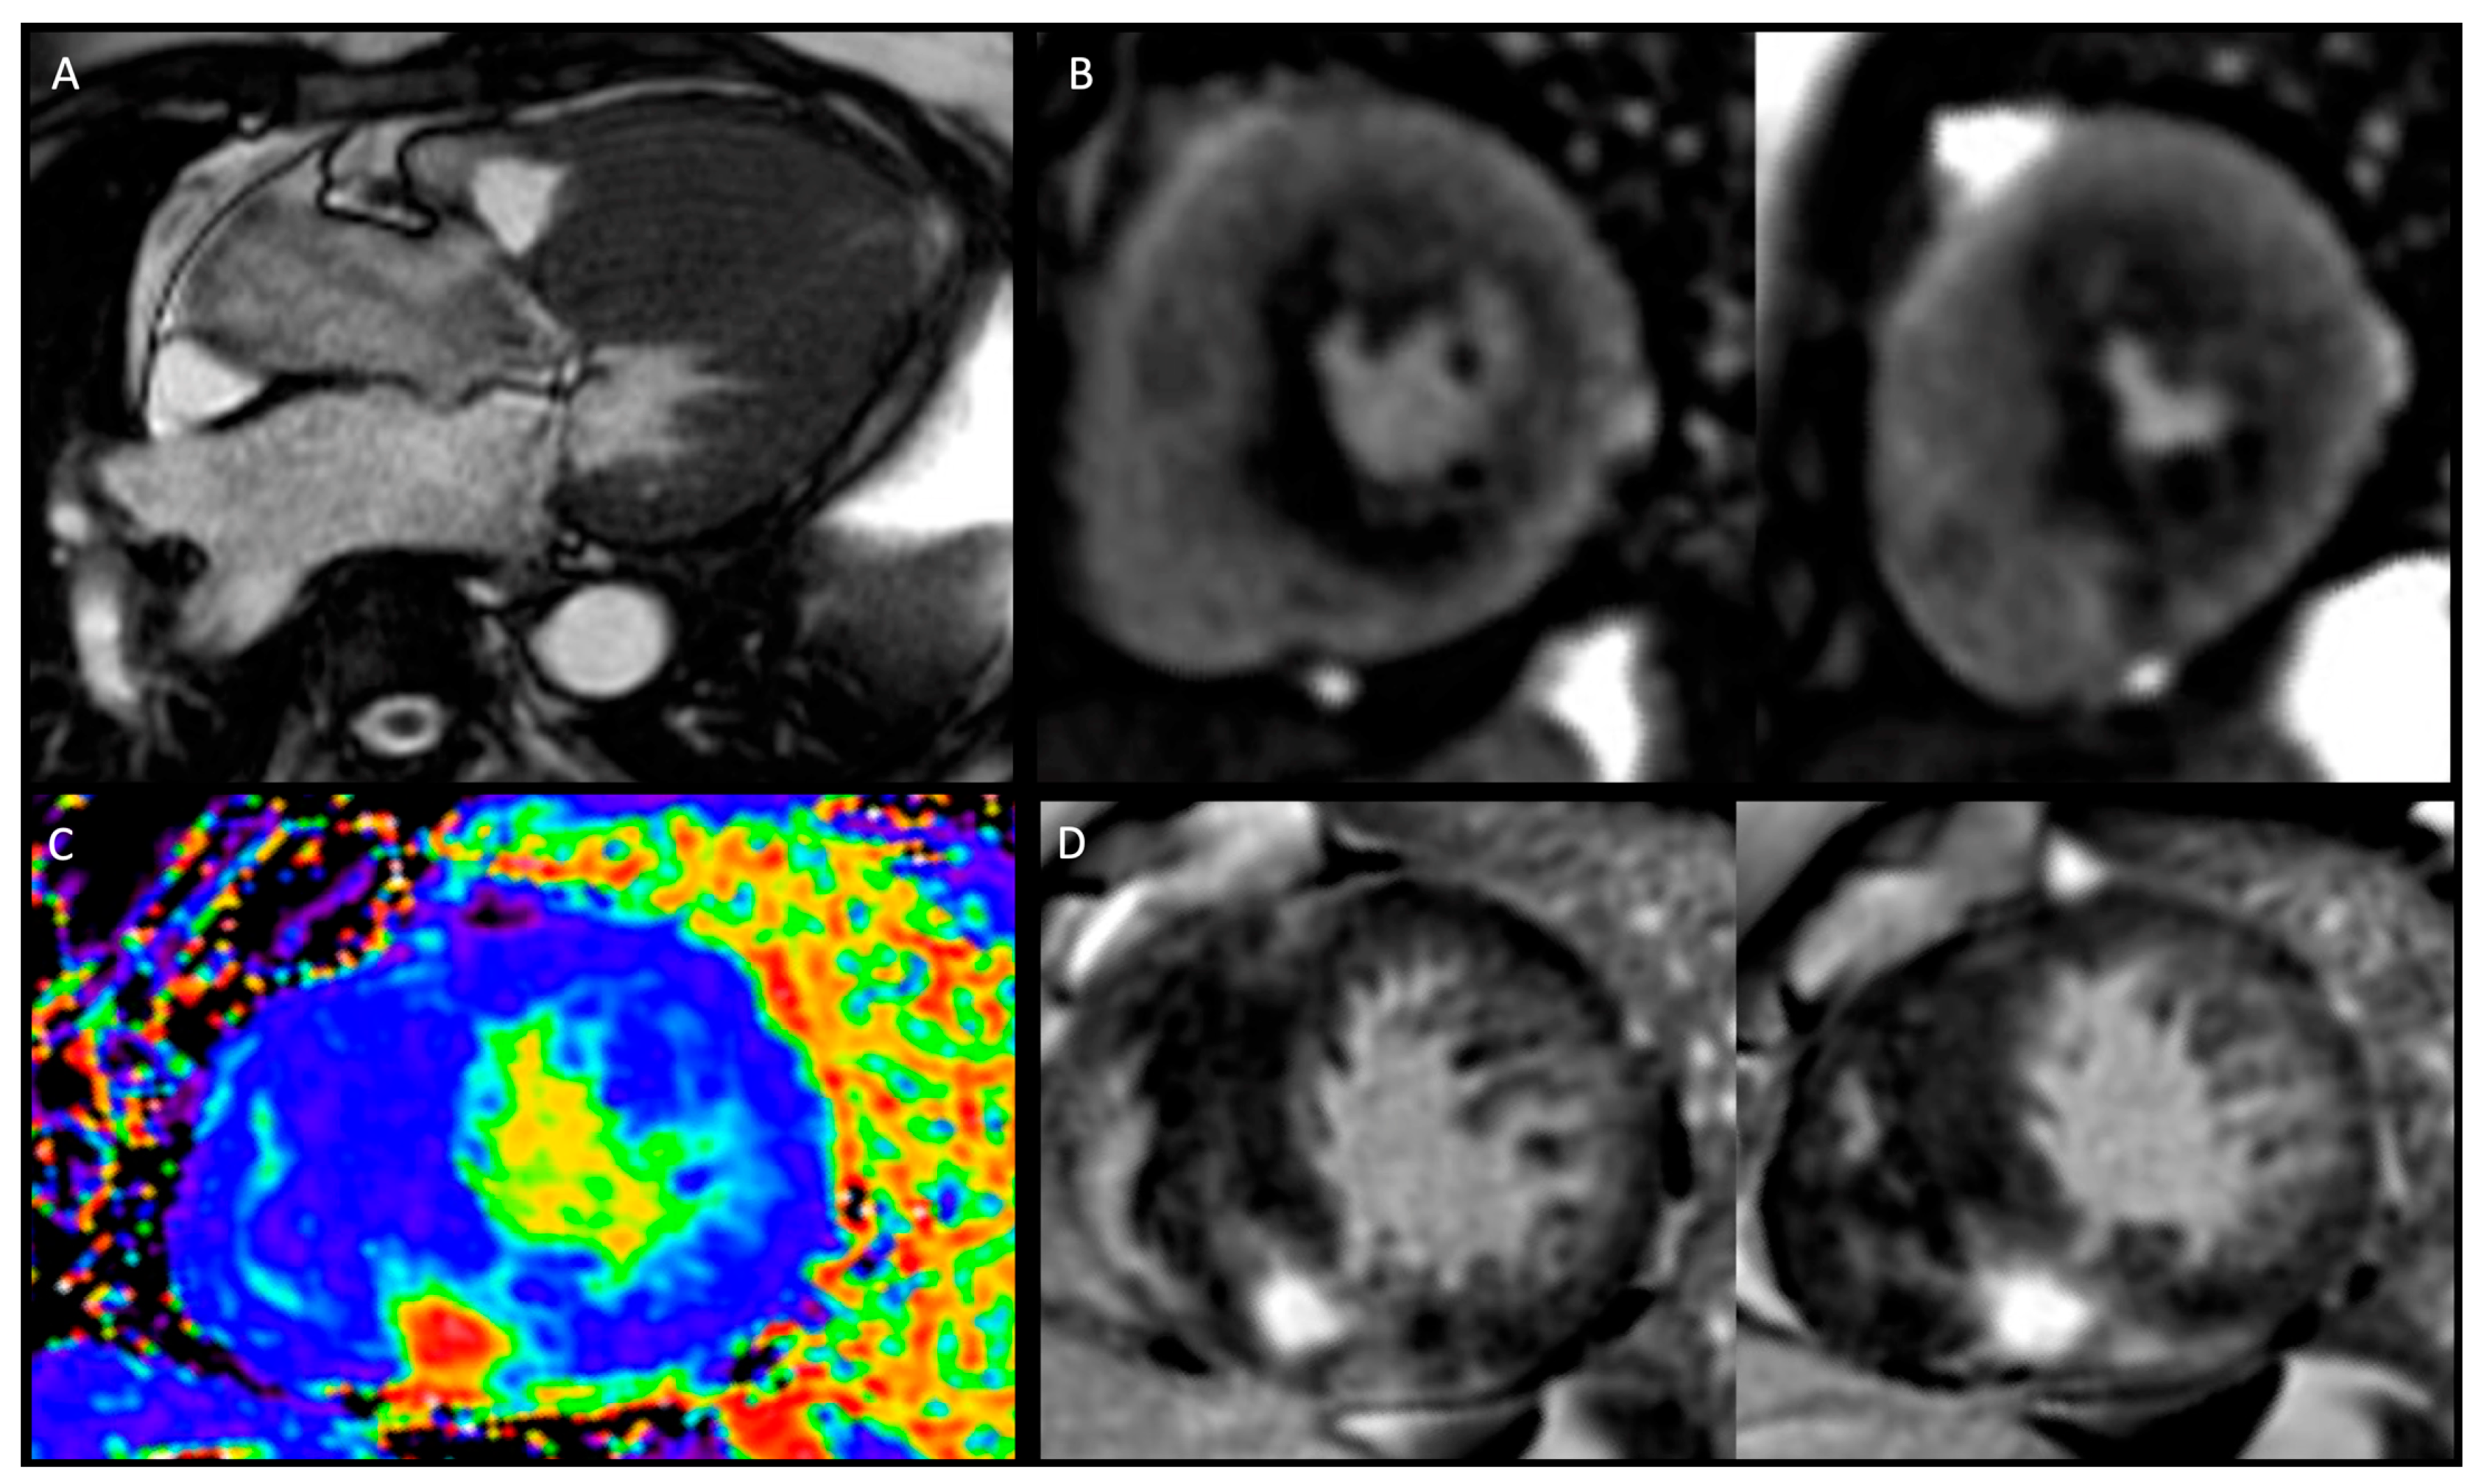

In the past, CMR was usually performed when echocardiography yielded inconclusive findings, but its use has become increasingly popular in recent years, and is now recommended in all patients with cardiomyopathy at initial evaluation (Class I, LoE B) [35]. While echocardiography is the first-line imaging modality and considered the standard for diagnosing HCM, it has limitations due to its dependence on adequate acoustic windows and challenges in obtaining cross-sectional images at the correct angles. Doppler assessment of LVOT mid cavity and apical gradients is crucial with echocardiography to guide management. In this regard, CMR complements echocardiography by enabling a complete and accurate assessment of all myocardial segments of the LV, here including the anterolateral wall, apical segments, septal junctions, and of the RV. It also allows evaluation of the papillary muscles (hypertrophy, abnormal insertion, feathering, and apical displacement) and detection of myocardial crypts. This comprehensive evaluation allows for precise reconstruction of cardiac size, morphology, function, and tissue characterisation. CMR with LGE is now recommended in HCM patients for diagnostic work up (Class I, LoE B) and further risk assessment (Class IIa, LoE B) [36]. Gadolinium-enhanced CMR plays a crucial role in precisely identifying myocardial fibrosis. The presence of LGE indicates replacement myocardial fibrosis and helps stratify the risk of ventricular arrhythmias and sudden cardiac death. Numerous studies have investigated the association between LGE and long-term outcomes in HCM and have consistently reported a significant positive relationship between presence of LGE and heightened risk of total and cardiovascular death, and HF. Native T1 mapping and extracellular volume fraction (ECV) are prolonged in HCM, indicating the presence of myocardial disarray and diffuse fibrosis. These values not only correlate with the risk of developing VT but also help differentiate HCM from other conditions. Tissue characterisation with CMR can also help to exclude other causes of LVH such as Fabry’s (low myocardial T1) or cardiac amyloidosis (elevated T1 and patterns of LGE). Coronary microvascular dysfunction can be further explored with stress CMR perfusion imaging as a valuable tool to detect perfusion abnormalities that might occur before the development of overt LVH or scarring in HCM gene mutation carriers due to microvascular obstruction, supply–demand mismatch, extravascular compressive forces, and elevated intraventricular pressures (Figure 1). An independent association between microvascular disease electrocardiographic abnormalities has been observed in subclinical HCM, also suggesting the arrhythmogenic potential of small vessel disease [37]. Furthermore, measurable changes in microvascular function and myocardial microstructure by diffusion tensor imaging represent novel early-phenotype biomarkers in the emerging era of disease-modifying therapy [38,39,40]. Further research is yet to be conducted to establish the role of this novel approaches [38].

Figure 1.

Phenotyping hypertrophic cardiomyopathy by CMR. Panel (A): Cine imaging—three chamber view depicting asymmetric left ventricular hypertrophy (LVH) with systolic anterior movement and left ventricular outflow tract turbulence. Panel (B): Adenosine stress perfusion imaging with perfusion defect in the areas of LVH and late gadolinium enhancement (LGE). Panel (C): extracellular volume mapping. Panel (D): LGE module: short-axis views showing right ventricular insertion point LGE and septal diffuse mid-wall LGE.